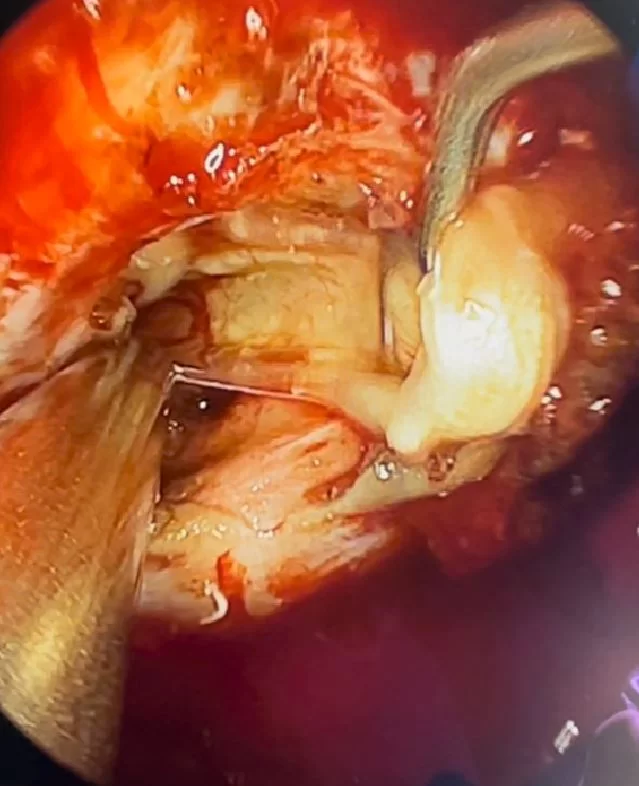

Αποφασίστηκε και διενεργήθηκε διαρρινική (δηλαδή μέσα από τη μύτη) ενδοσκοπική αφαίρεση του όγκου. Η αφαίρεση ήταν ολική.

Τα κρανιοφαρυγγιώματα είναι καλοήθεις όγκοι οι οποίοι μπορούν να αναπτυχθούν τόσο σε παιδιά όσο και σε ενήλικες. Συνήθως “κολλάνε” ισχυρά με τους πέριξ ιστούς και πιέζουν τα οπτικά νεύρα. Συχνά, η ολική αφαίρεση είναι δύσκολη και απαιτεί κρανιοτομία, δηλ. προσέγγιση του όγκου μέσα από τομή στο κρανίο.

Στη συγκεκριμένη ασθενή επιλέξαμε να αφαιρέσουμε τη βλάβη με τη βοήθεια του ενδοσκοπίου, μέσα από τη μύτη. Η ενδοσκοπική αφαίρεση επιτρέπει να ελεγχθεί πλήρως ολόκληρη η περιοχή του εφιππίου και να επιτευχθεί τελικά ολική αφαίρεση του όγκου χωρίς τομή στο κρανίο!